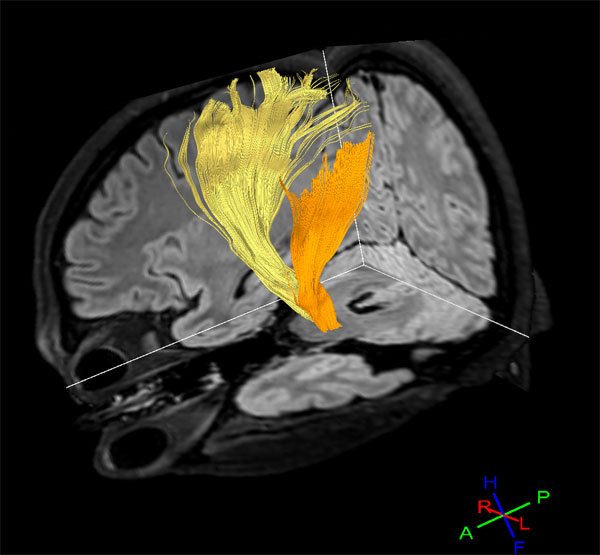

Diffusion Tensor Imaging - Fibertrak

Diffusion Tensor Imaging Fibertrak